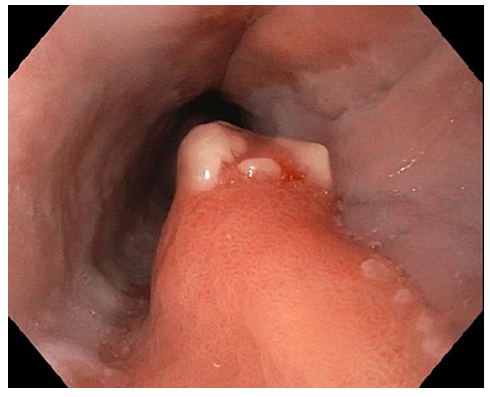

We repeated upper gastrointestinal endoscopy and observed two areas of pink mucosa oppositely positioned in the proximal esophagus (18 cm from the incisors), suggesting GH. One of these areas had a polypoid morphology with congestive, friable, and erosive mucosa measuring approximately 12 mm (Fig. 1). Narrow-band imaging evaluation showed a preserved glandular, vascular pattern (Fig. 2). Biopsies were taken from the lesion and anatomopathological assessment revealed fragments of gastric-type mucosa, consisting of occasional poorly oriented foveolar structures compatible with ulcerated GH. There was no metaplasia or dysplasia. No H. pylori-like microorganisms were observed in GH (Fig. 3). A multidisciplinary approach led us to decide on an expectant strategy due to its probable benign course. A follow-up endoscopy was performed, and the polypshowednosignificant changes from the prior examination.

Fig. 2 Narrow-band imaging assessment of the polyp showing a preserved glandular and vascular pattern.